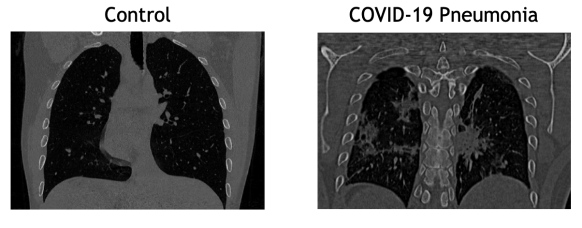

Refer to caption

Fig. 1: Slices of two CCT images of a control (left) and a pneumonia caused by COVID-19 (right). Note some clear artifacts in COVID-19 image.

The dataset employed in this work was provided by HT Médica, a company specialized in radiology that offers innovative solutions for image diagnosis. The dataset comprises 513 CCT images, including 100 control patients and 413 characterized as depicting pneumonia associated with COVID-19. All images were obtained as part of patient’s routines clinical care during the first wave of the COVID-19 pandemic in Spain (March to June 2020). Data were anonymized before being used in this study following the requirements stated by medical ethics committees. Figure 1 shows a slice of a CCT scan from a control (CL) and a patient suffering from pneumonia (PNEU).